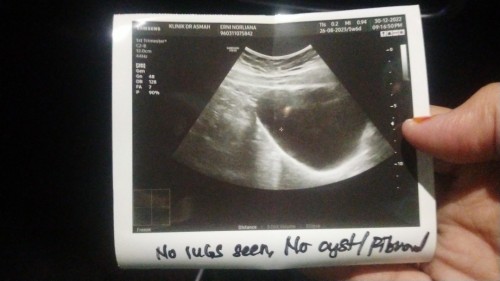

Normal ke UPT (-VE) & SCAN KANTUNG TAK NAMPAK TAPI PREGNANT?

Symtom-symptom pregnant tu banyak. Memang tak pernah ada time period. Tapi bila buat test semua -ve. Ke perlu tunggu lama lagi?

Ada beberapa sebab juga... 1.mungkin pregnant tp belum nampak kantung.. Yang jdi negatif mungkin sbb waktu urine test x sesuai 2. Mungkin juga tu pms sahaja, sbb ada masa hormon badan kita akan berubah.. Mgkin sblum kawen xde pms.. Tp lps kawen dpt pms.. Mgkin.. Sbb dah scan pon xnmpk, upt pon negatif, if let say upt positive then scan xnmpk.. Mgkin sbb kecik lgi atau.. Kandungan luar rahim.. Lain pulak kes nye.. Pape pon semoga ade rezeki ye sis